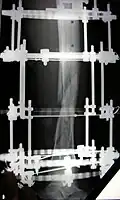

Процедура лечения открытого перелома большой и малой берцовой костей аппаратом Илизарова. Фотографии и рентгенограммы одного и того же пациента в течение курса лечения. Снимки 2 — 6 сделаны через четыре недели после перелома (две недели после наложения аппарата).

Вид аппарата Илизарова спереди и слева (перелом чуть выше черного металлического кольца).

Рентгенограмма места перелома сразу после наложения аппарата Илизарова

Рентгенограмма места перелома (через два месяца после перелома), № 1

Рентгенограмма места перелома (через два месяца после перелома), № 2